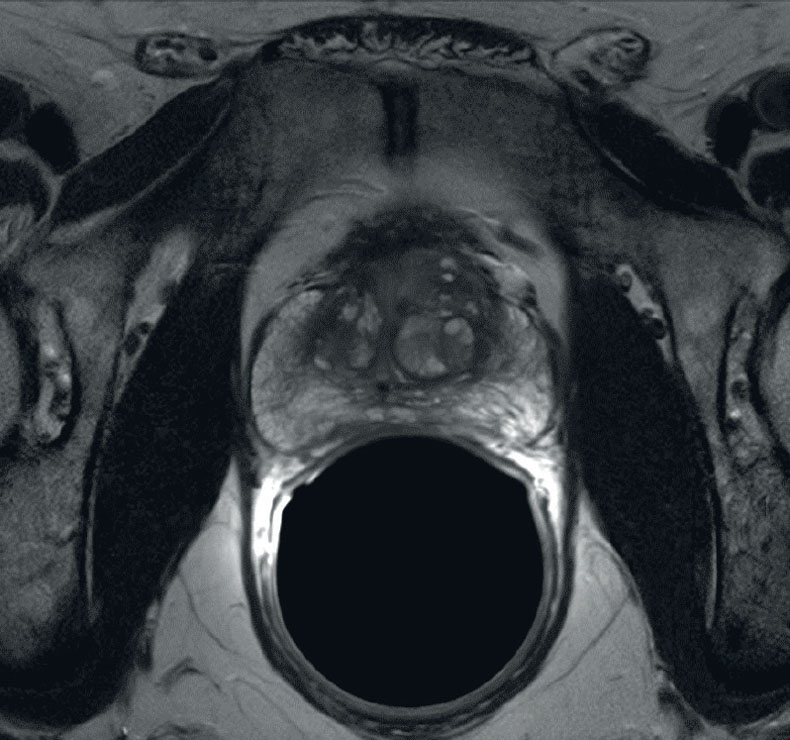

Additional imaging studies include an MRI of the prostate, generally with endorectal coil. If the PSA is > 20 then a bone scan is reasonable. A transrectal ultrasound is an intrinsic part of the biopsy in recent years. Peripheral zone cancers can be seen on the ulltrasound with hyper-echoic lesions in 69% of the cases. CT of the pelvis and prostate are used in radiotherapy treatment planning. Discrepancies between CT and MRI on fused images may exist (Roach):

There is significant variation of contours and techniques. The apex and base are regions most susceptable to variation. 3D perspectives help signficantly reduce this variation using transverse, sagital and coronal projections to determine the true extent of the prostate. More recently contouring atlases have been developed by the RTOG with grant assistance from the NCI and are available here. The following images are obtained from the RTOG contour atlases as an excerpt demonstrating areas of potential uncertainty.

Prior TURP may also be a contraindication as this may allow seeds to overdose the urethra, which could lead to stricture or post-implant incontinence. With modern peripheral loading techniques, this may be less a contraindication than previously thought as complications have decreased. Linked seeds may be advantageous in this setting. Before any brachytherapy in a patient with a history of TURP can be considered, detailed imaging of the extent of TURP should be obtained and considered mandatory. T2 MRI and T1 post gadolinium will be helpful.